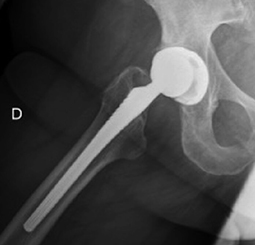

A 66-year-old woman, reported sudden functional inability to walk accompanied by snapping on limb mobilization 43 months after total right hip replacement (Corail, Pinnacle cup 48, ceramic head 32, +4 10° oblique PE oriented posteroinferiorly). Radiographic findings were consistent with PE dissociation with adequate acetabular abduction and anteversion, 41° and 28° respectively, as measured in plain X-rays (Figure 1) (Figure 2). During revision surgery, adequate component orientation was confirmed. The insert (+4 10° oblique) showed signs of wear and deformation in the posteroinferior elevated rim, (Figure 3). The oblique insert did not provide greater stability but caused impingement, so it was exchanged to a ceramic insert and a 32+5 head.

Figure 2. Lateral hip view. Radiographic findings consistent with polyethylene dissociation. Eccentric position of the prosthetic head. Case 2

Figure 2